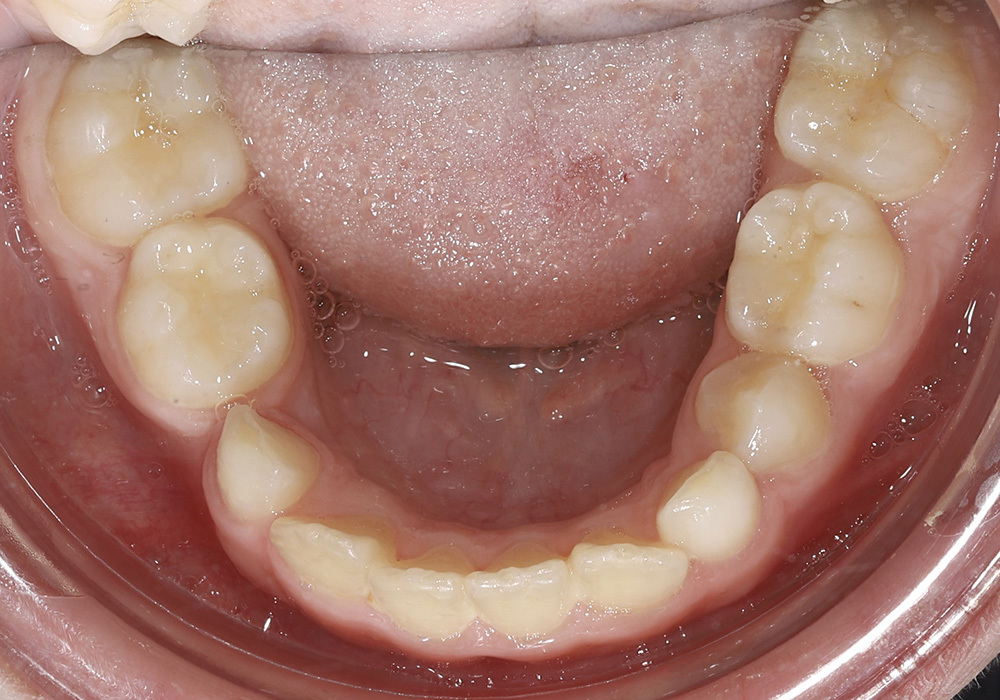

Коррекция прикуса и выравнивание зубных рядов у подростка несъёмной ортодонтической техникой